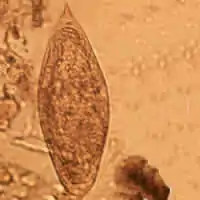

| Egg of Schistosoma intercalatum | |

The clinically defining characteristic of most schistosome species are their eggs' size and shape. The eggs of Schistosoma intercalatum have a terminal spine and tend to be moderately larger than those of S. haematobium (approximately 130 × 75 μm). The origin of the name 'intercalatum' is from the observation that their eggs are of an intermediate range between the smaller S. haematobium and larger S. bovis.[2] These eggs are unique because they will stain red when exposed to the Ziehl-Neelsen technique, aiding in identification.[3] When viewed using scanning electron microscopy, it can be observed that the S. intercalatum's surface has a much lower amount of integumental elevations, or bosses, than S. mansoni. This feature is consistent with the tegument appearance of other terminally spined schistosomes.[4]

Diagnosis is usually made using clinical and epidemiological information. Infection with S. intercalatum can be distinguished from that of S. mansoni or S. haematobium based on where eggs manifest outside the body and the morphology of the eggs. In Africa, the only species of schistosome are S. intercalatum, S. mansoni, and S. haematobium. S. haematobium causes urinary schistosomiasis, so eggs will be shed in the urine; S. mansoni and S. intercalatum reside in the mesenteric venous plexus, so eggs will be shed in the feces.[5] Looking at the stool specimen under a microscope, the species can be distinguished; S. intercalatum eggs have a terminal spine (as seen in the figure above) and S. mansoni eggs have a lateral spine.[14]